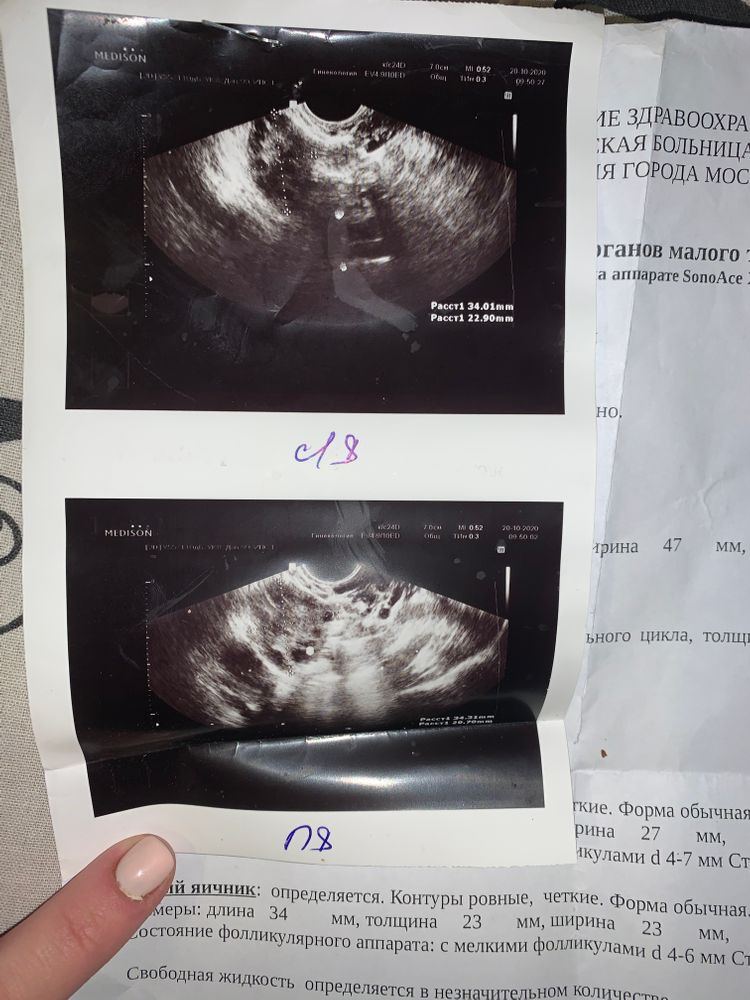

Если и есть киста,то уже с нынешнего цикла, поэтому октябрьское узи не информативно , нужно сделать повторно и узнать вид кисты

Так узи от 20 октября. Что угодно вырастит за месяц. Какая хоть киста: фолликулярная или желтого тела?